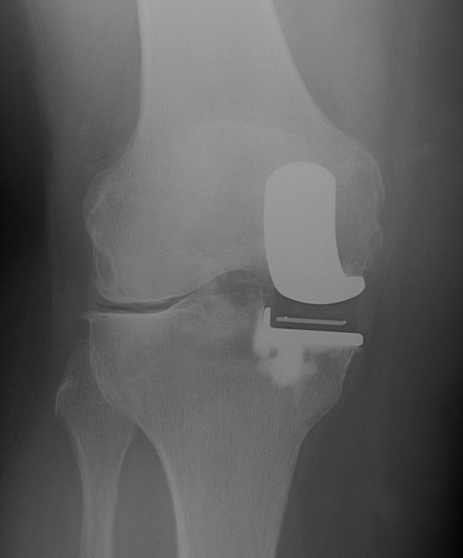

Patient 2